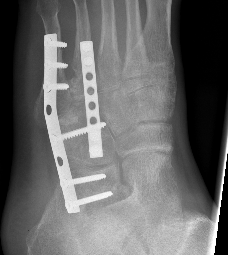

Bridge plating

Severe comminution / lateral column shortening

- consider temporary distractor / external fixation to obtain length

- calcaneum to 4th / 5th metatarsal plate

- non-weight bearing until union then remove plates (typically 12 weeks)

AO foundation bridge plating cuboid

cuobidcubcub